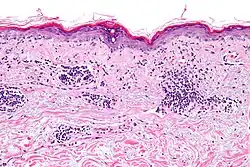

As many as 70% of people with lupus have some skin symptoms. The three main categories of lesions are chronic cutaneous (discoid) lupus, subacute cutaneous lupus, and acute cutaneous lupus. People with discoid lupus may exhibit thick, red scaly patches on the skin. Similarly, subacute cutaneous lupus manifests as red, scaly patches of skin but with distinct edges. Acute cutaneous lupus manifests as a rash. Some have the classic malar rash (commonly known as the butterfly rash) associated with the disease.[17] This rash occurs in 30–60% of people with SLE.[18]

Discoid (cutaneous) lupus is limited to skin symptoms and is diagnosed by biopsy of rash on the face, neck, scalp or arms. Approximately 5% of people with DLE progress to SLE.[80]

Several techniques are used to detect ANAs. The most widely used is indirect immunofluorescence (IF). The pattern of fluorescence suggests the type of antibody present in the people's serum. Direct immunofluorescence can detect deposits of immunoglobulins and complement proteins in people's skin. When skin not exposed to the sun is tested, a positive direct IF (the so-called lupus band test) is evidence of systemic lupus erythematosus.[101]